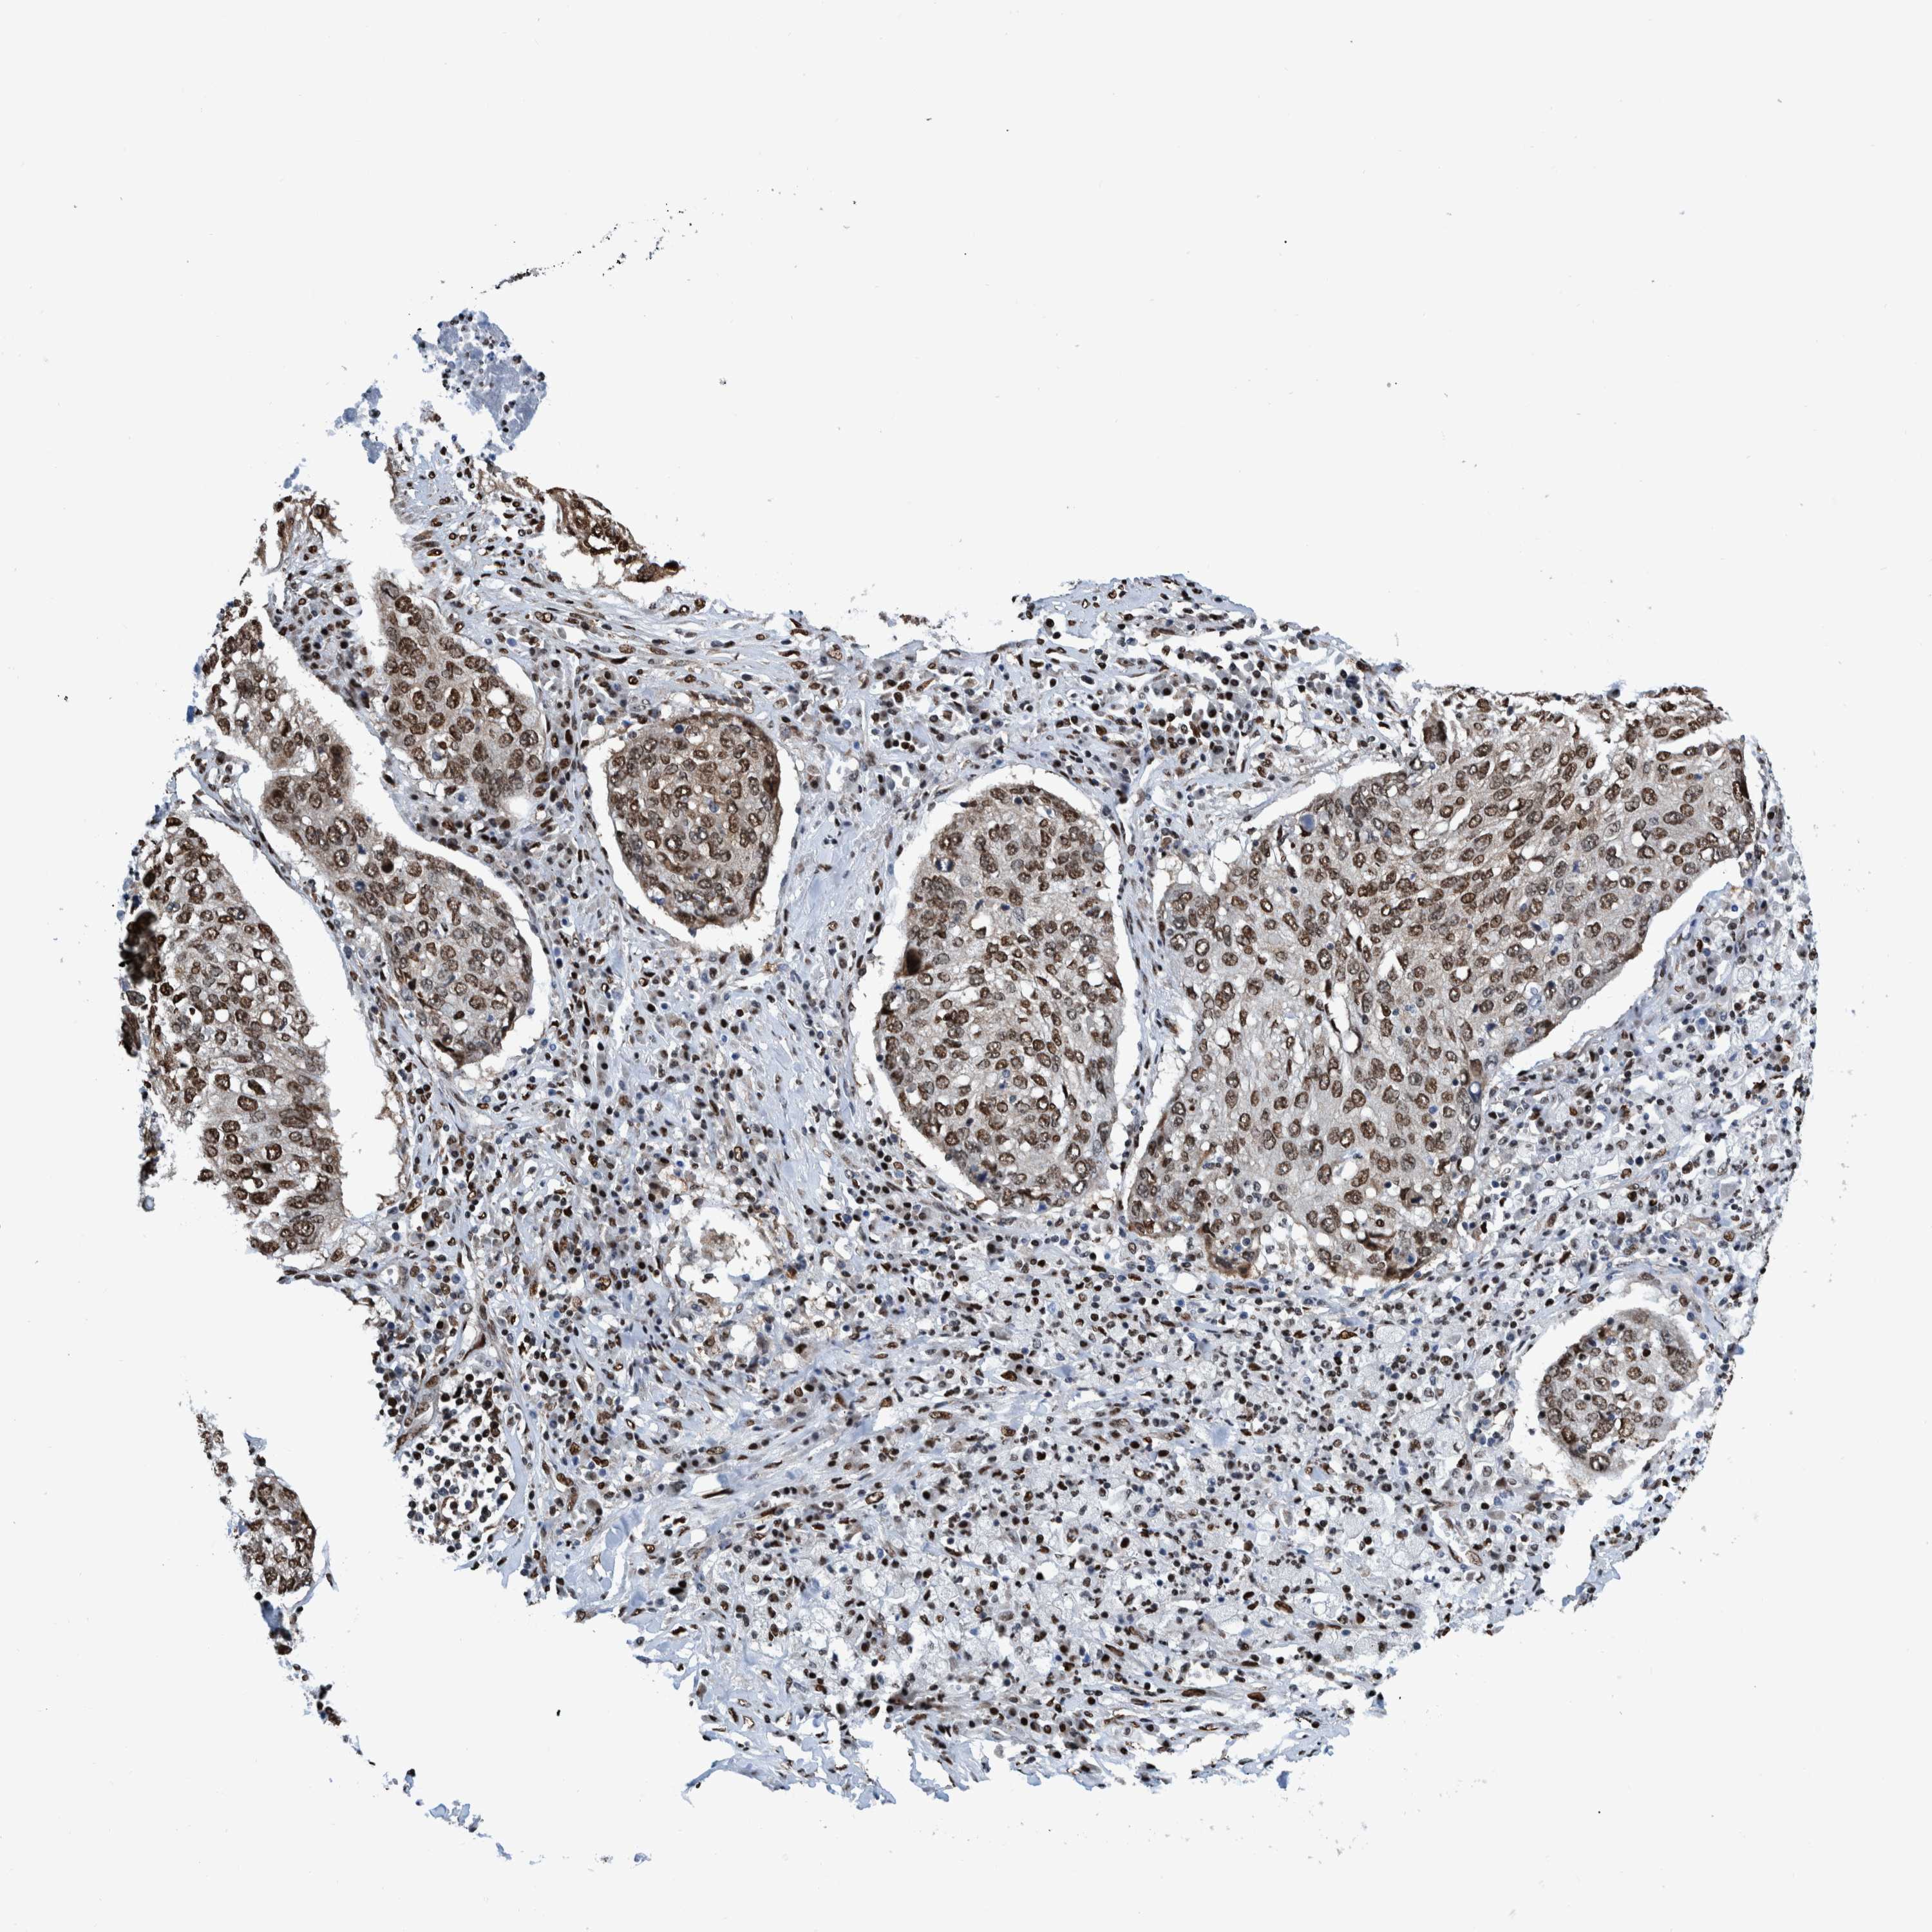

CANCER LUNG CANCER Show tissue menu